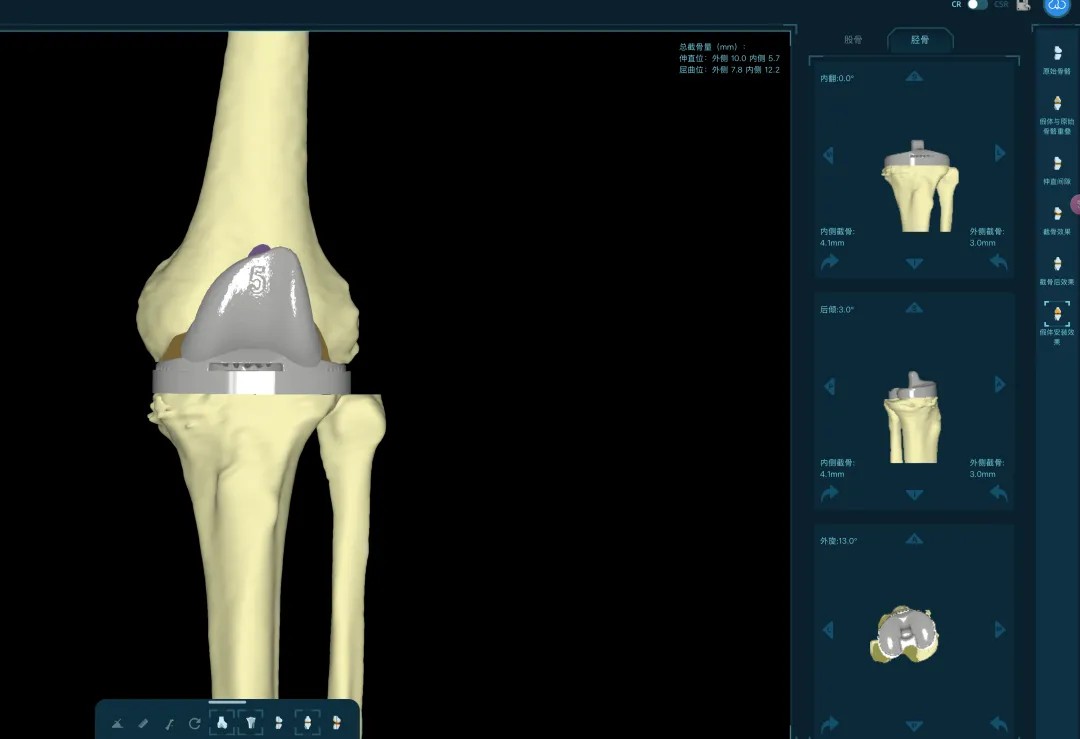

清創(chuàng)只是第一步,如何在一片“復(fù)雜地形”中重建一個(gè)穩(wěn)定、功能良好的膝關(guān)節(jié),是更大的挑戰(zhàn)。為此,團(tuán)隊(duì)引入了計(jì)算機(jī)輔助手術(shù)規(guī)劃系統(tǒng)。

通過患者的CT數(shù)據(jù),系統(tǒng)構(gòu)建出膝關(guān)節(jié)的三維數(shù)字模型,精確評(píng)估骨缺損的范圍與形態(tài)。醫(yī)生可以在虛擬空間中,提前模擬手術(shù)過程,為患者“量體裁衣”,規(guī)劃出假體安放的最佳位置、角度以及所需填充骨缺損的特殊墊塊型號(hào)。

“這相當(dāng)于在真實(shí)戰(zhàn)斗前,進(jìn)行了一次全方位的沙盤推演。”羅軍介紹,這種規(guī)劃確保了手術(shù)的精準(zhǔn)度,縮短了手術(shù)時(shí)間,也為使用先進(jìn)的翻修假體系統(tǒng)做好了完美鋪墊。

本次手術(shù)的核心,是采用了Evolution® ECCK膝關(guān)節(jié)翻修系統(tǒng)。該系統(tǒng)專為應(yīng)對(duì)翻修手術(shù)中常見的嚴(yán)重骨缺損、韌帶功能不全等極端復(fù)雜情況而設(shè)計(jì)。

其模塊化的組件提供了前所未有的靈活性,就像一套高精度的“工程套件”,允許醫(yī)生在術(shù)中根據(jù)實(shí)際骨缺損情況,自由組合不同尺寸的墊塊、延長(zhǎng)桿等部件,實(shí)現(xiàn)關(guān)節(jié)線和力學(xué)穩(wěn)定性的個(gè)體化重建。